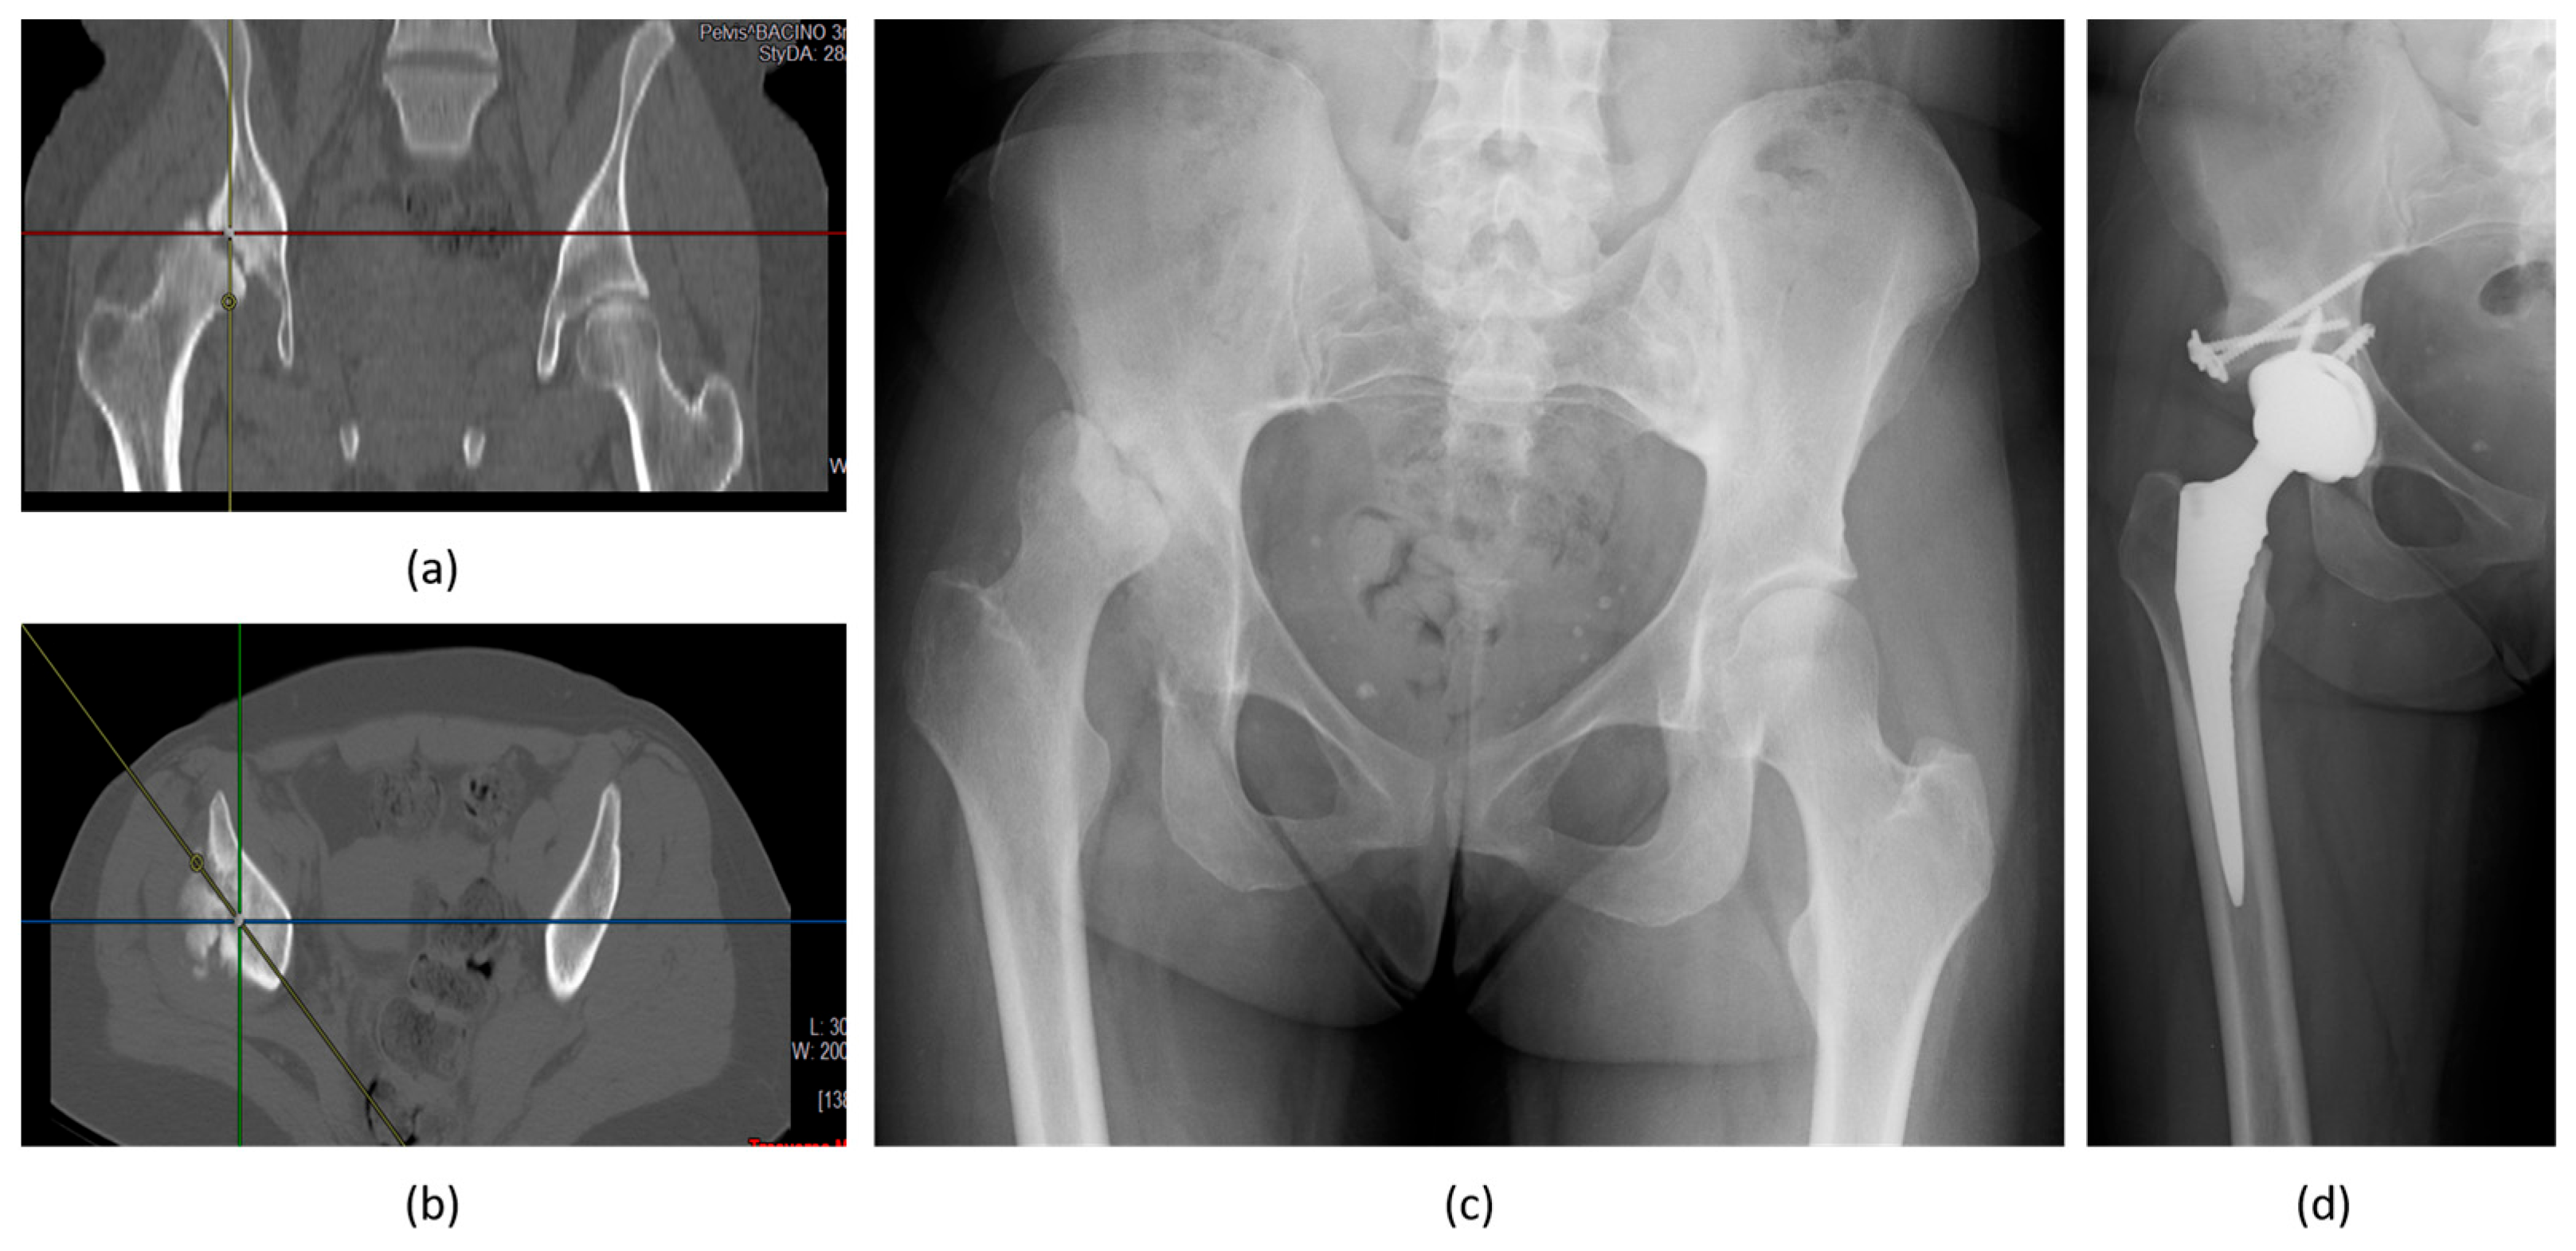

Injuries represent another intriguing chapter of sex- and gender-specific orthopedics. According to a recently published current concepts review [44], encompassing 28 studies, sex- and gender-related differences could be identified in several key areas related to the management of total hip arthroplasty: namely, (i) the choice of surgical approach, use of robotic surgery, considerations of scar appearance, and selection of implants; (ii) outcomes and complications following surgery; (iii) the impact on sexual activity post-total hip arthroplasty; and (iv) psychological well-being and daily functional capabilities. Sex- and gender-specific analyses revealed that female patients may require more tailored considerations during the preoperative, operative, and post-operative stages to enhance clinical and functional results, minimize the likelihood of complications, and ensure patient satisfaction. The success of the total hip arthroplasty procedures was found to be significantly affected by factors related to sex and gender, which necessitates a careful evaluation and the adoption of specifically devised interventional strategies in surgical patients to enhance their satisfaction with the surgery’s outcomes and lower the incidence of sex-differentiated post-operative complications.

A recently published, retrospective analysis of 16,359 cases from the “German Trauma Registry” [48] confirmed the “morbidity–mortality paradox” in the orthopedic setting. Women were found to be more commonly affected by pelvic fractures than men (with an incidence of 38.4/100,000 versus 33.4/100,000 among men). Of note, when categorizing the population into three age groups (young: under 35 years, middle-aged: 35–65 years, and elderly: over 65 years), it was observed that men were more prevalent in the younger two categories (Figure 3), while women were more common in the elderly group. Across these age groups, men reported a higher incidence of acetabular fractures, whereas women exhibited a higher incidence of unstable pelvic girdle fractures. Men also showed a higher rate of fractures caused by polytrauma. Furthermore, rates of surgery, morbidity, and mortality related to these injuries were higher in men compared to women.